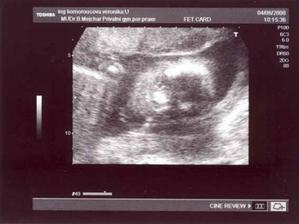

21.2. - šla jsem na první kontrolu, Zdenda musel do Berouna vyzvednout rozbité auto, tak dorazil k lékaři později - Bušilo mi srdíčko, jestli bude vše v pořádku a bylo!!! V autě jsme si pak společně prohlíželi s dojetím první fotku našeho miminka - byl to zatím jen gestační váček

29.2- další velké nervy, čekání na srdíčko - na UTZ byla vidět krásná srdeční akce, Zdenda byl se mnou v ordinaci a měli jsme obrovskou radost!!!...jsme nyní na začátku 8.tt (7+0) - to je ještě dlouhá cesta....